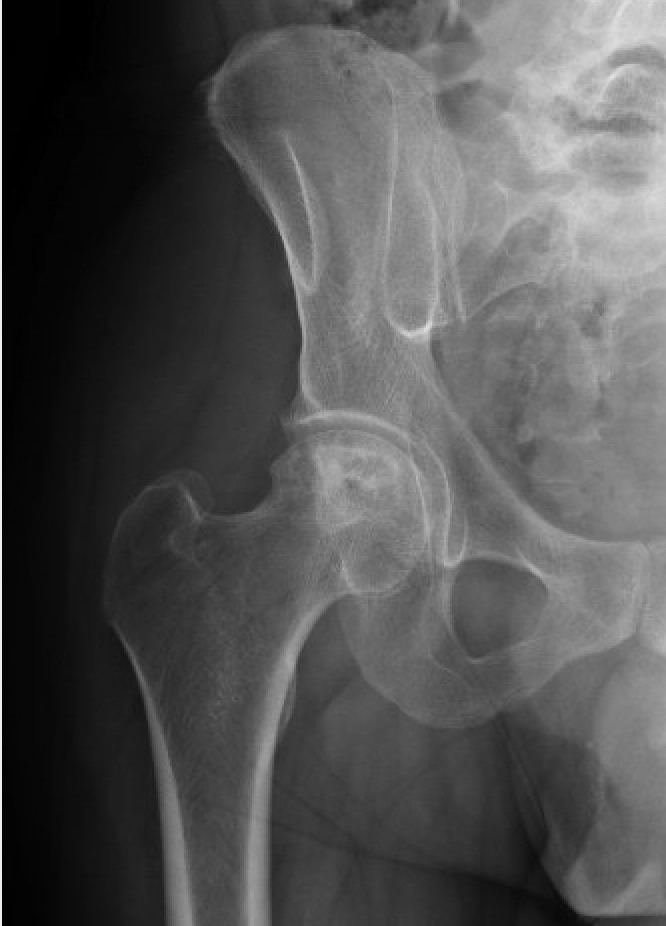

Pelvis/Hip Case 1 Answer

Answer: Avascular Necrosis of the Femoral head